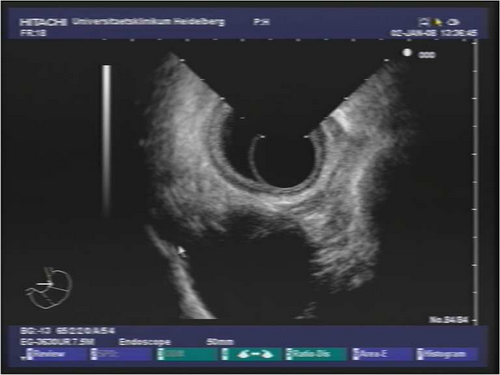

Endosonografie: In der durchgeführten Endosonographie zeigte sich ein ulzerierter Magentumor im Bereich des Korpus-/Antrumübergangs. Endosonographisch wird die Muskularis infiltriert, an einigen Stellen auch die Serosa, benachbarte Strukturen sind nicht infiltriert, somit uT3 (max. Dicke 9 mm). Es finden sich lokoregionär auch im Bereich des Tr. coeliacus mehrere LK bis 10 mm. Beim Rückzug stellten sich zudem paraösophageal mehrere deutlich vergrösserte, echoarme und polyzyklisch begrenzte, suspekte LK dar.